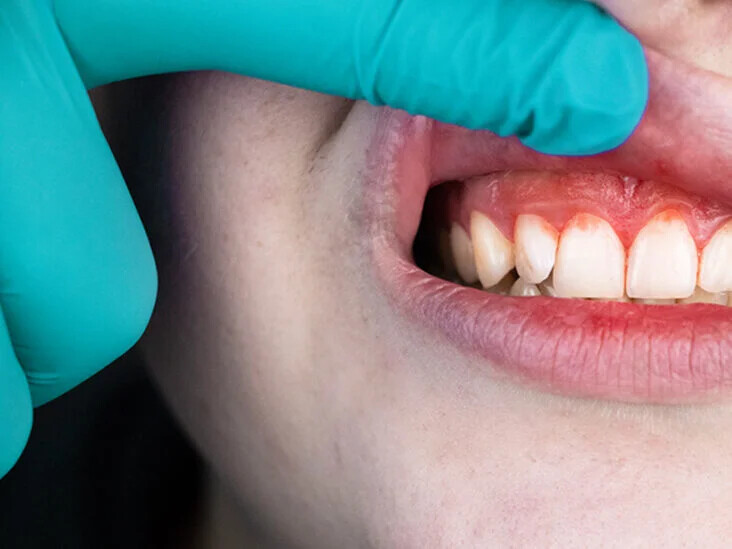

If there is swelling around just one tooth in your mouth, it may be because you didn't brush or floss correctly, leaving behind food debris that cause tooth cavities and inflammation in the neglected area. Over time, such inadequate oral hygiene can also lead to gum disease. Be on the lookout for pale, red or swollen gums, as well as bleeding while brushing, pus coming from the tooth, a loose tooth, or persistent bad breath and taste.

2. Gum Disease

A common trigger of a swollen gum around one tooth, gum disease is a prevalent condition for which you should be on guard each time you brush. In its earliest stages, the condition's symptoms show up as red and swollen gums that, although painless, might still bleed. As the disease progresses, it can cause loose teeth due to gums that have pulled away in certain spots.

3. Abscessed Tooth

An abscessed tooth is another very common cause of local gum swelling and indicates an infection in or around your tooth. This can often come from an untreated cavity that causes germs to spread through and infect your tooth. Keep in mind that an abscess can cause irritation and ultimately cost you the tooth if left untreated. Telltale signs include throbbing pain, red or swollen gums, a swollen jaw or face, a tender or sore tooth, a fever, and even a salty taste in your mouth. Because treatment is required for an abscessed tooth, your dentist may give you antibiotics for the infection, a root canal to remove the infected pulp, or extract the tooth entirely depending on the severity.